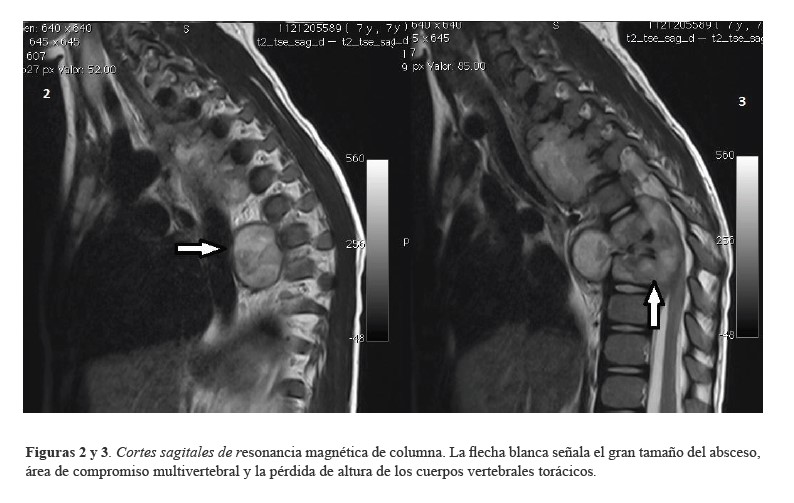

Por antecedente de proceso viral previo al cuadro clínico, se sospechó en primera instancia mielitis post infecciosa. Se solicitó resonancia magnética (RM) cerebral y de columna vertebral, se realizó desparasitación con albendazol y se ordenaron bolos de metilprednisolona, los cuales fueron completados por tres días sin observarse mejoría clínica. La RM cerebral simple y contrastada fue normal; la RM de columna a la altura de C7 hasta T4 y T5 y en T6 y T7 mostró alteración de las señales en los cuerpos vertebrales, con hiperintensidades en T2 e hipointensidades en T1, acompañándose de masa pre y paravertebral hipointensa en T1 e hiperintensa en T2, con ligera pérdida de altura en los cuerpos vertebrales T1 a T4, T6 y T7 (Figuras1-3), hallazgos interpretados por radiología como compatibles con linfoma.

Figuras 2 y 3. Cortes sagitales de resonancia magnética de columna. La flecha blanca señala el gran tamaño del absceso, área de compromiso multivertebral y la pérdida de altura de los cuerpos vertebrales torácicos.

En niños, la TB afecta principalmente el sistema pulmonar y es poco frecuente la localización espinal. La presentación que compromete el hueso es más peligrosa, pues causa destrucción ósea, deformidad y paraplejía. El caso de esta paciente se presenta con cuadro de compromiso medular de predominio torácico, coincidiendo con lo reportado en la literatura, donde se ha descrito que la TB espinal afecta con más frecuencia las áreas torácicas inferiores y lumbares superiores de la columna (12). Los varones se ven afectados con mayor frecuencia en una relación 4:3 (13); como se ha mencionado, sin embargo, en este caso se trataba de una niña. Se han descrito dos formas de presentación: la espondilodiscitis (clásica) y la espondilitis sin compromiso del disco (atípica), siendo más frecuente el compromiso de múltiples vértebras contiguas (9), lo que se correlaciona con lo observado en este caso. El compromiso espinal resulta de la diseminación hematógena del Mycobacterium tuberculosis en la vasculatura del hueso esponjoso de los cuerpos vertebrales (14). El sitio de infección primaria puede ser pulmonar u otro foco extra óseo, como nódulos linfáticos, sistema gastrointestinal u otra víscera. La TB pulmonar no se detecta en el 50% de los casos de TB espinal (13), como ocurrió en el presente caso. Al llegar los bacilos al cuerpo vertebral son capturados por monocitos, células epitelioides y células de Langerhans. La reacción granulomatosa subsiguiente conduce a la expansión del cuerpo vertebral y, finalmente, al colapso (14). En el caso descrito, en el momento de la realización de las imágenes, se observaba ligera pérdida de la altura de los cuerpos vertebrales, sugiriendo un avanzado compromiso de la enfermedad.